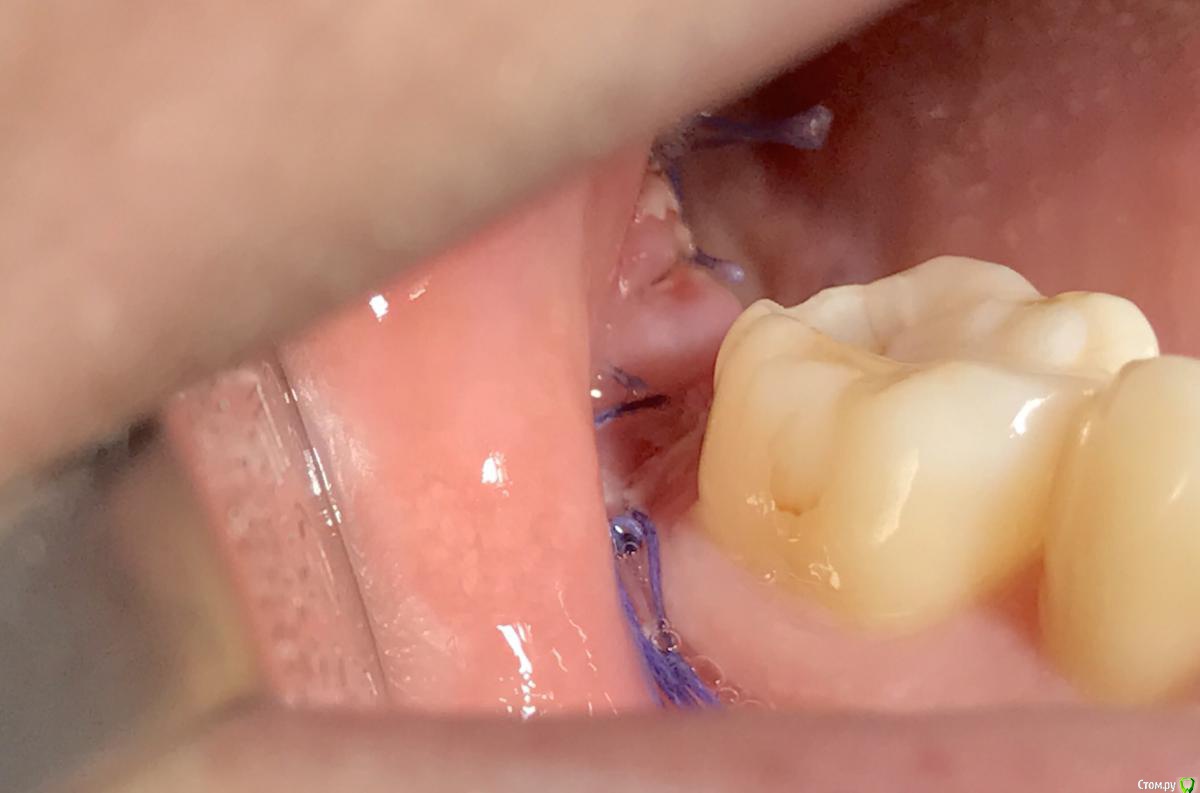

колесников Опубликовано 1 апреля, 2017 Автор Поделиться Опубликовано 1 апреля, 2017 Из свежего Ссылка на комментарий

колесников Опубликовано 2 апреля, 2017 Автор Поделиться Опубликовано 2 апреля, 2017 Да,викрил г,но в данном случае не принципиально,основной шов внутренний , область очень чувствительная,не колется и на том спасибо.После удаления гигиена обычно по нулям,так что не особо важно что там было в полости рта "до". Мне важно чтобы там где будет новый лоскут все было гладко и чисто,непосредственно перед удалением гигиена 37,47. Ссылка на комментарий

колесников Опубликовано 2 апреля, 2017 Автор Поделиться Опубликовано 2 апреля, 2017 Тройной лоскут , вид через 5 -7дней. Снимок "до". И благодарность за скорое заживление 6 Ссылка на комментарий